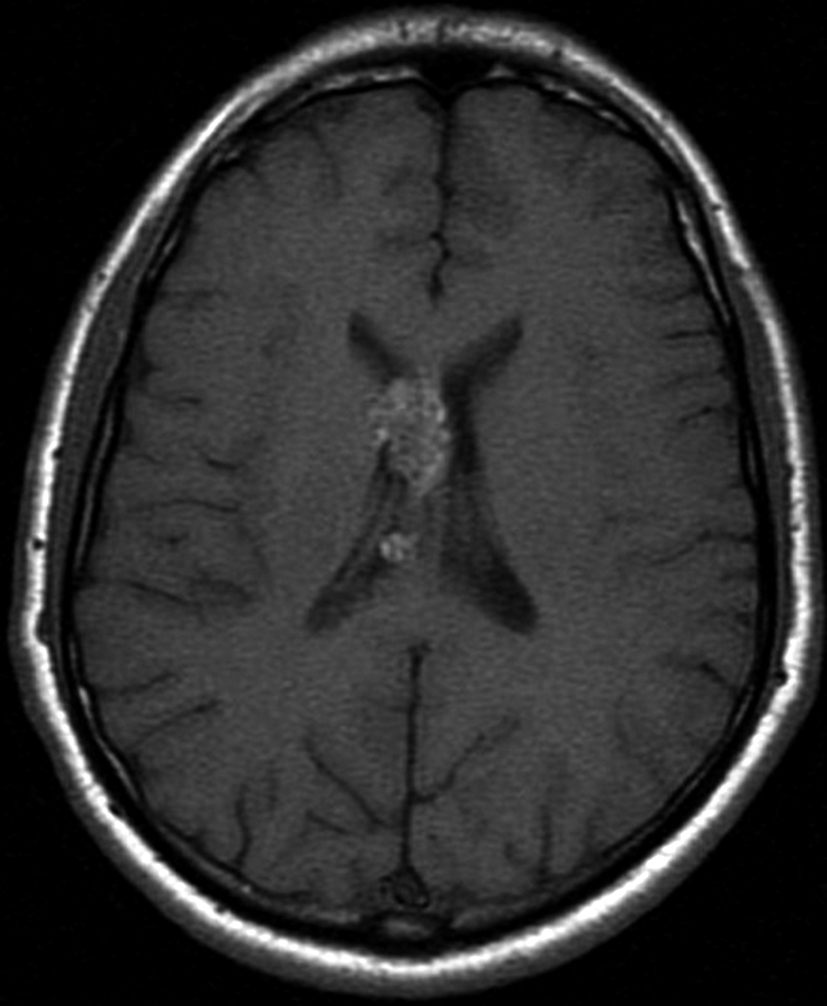

Con los hallazgos tomográficos, no se efectúan planteos diagnósticos y se realiza una resonancia magnética con la finalidad de obtener más datos semiológicos en busca de una aproximación diagnóstica. Se realizó el estudio por medio de secuencias T 1, FSE T 2, FLAIR, SWI y Difusión, en cortes axiales, FSE coronal y sagital T 1. Se realiza la administración de gadolinio DTPA en los tres planos. Se evidencia la lesión bien definida a nivel del ventrículo lateral derecho, que involucra al tronco del cuerpo calloso (Figura 2- C y 3- B). Presenta intensidad de señal heterogénea en secuencias T1 y T2 (Figura 3 y Figura 4). En secuencia ecogradiente se observa una señal marcadamente hipointensa y heterogénea, con un halo hipointenso bien definido (Figura 2- C). No presenta realce significativo tras la administración de Gadolinio (Figura 2- B) y en la secuencia de difusión no presenta restricción.

Figura 2 Resonancia magnética.

a) Imagen axial T1, lesión intraventricular con intensidad de señal heterogénea.

b) Tras la administración de Gadolinio no presenta realce significativo.

c) Imagen axial en secuencia ecogradiente donde se evidencia la lesión

hipointensa y heterogénea. Se observa la extensión de la lesión al cuerpo calloso.